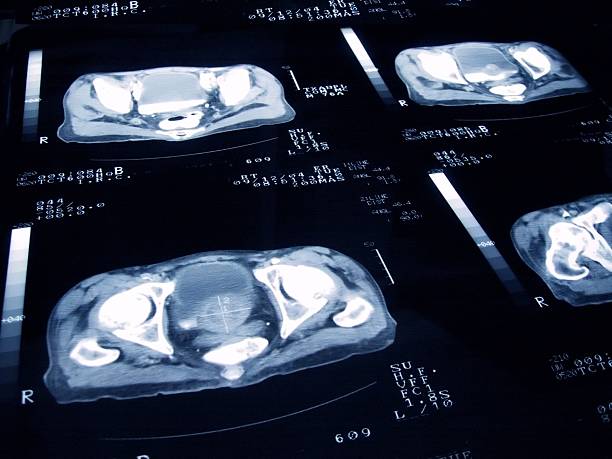

전립선 비대증(BPH, Benign Prostatic Hyperplasia)은 전립선 조직이 비정상적으로 커지면서 요도를 압박해 배뇨 장애를 유발하는 질환입니다.

대개 50대 이후에 많이 발생하며, 남성 호르몬과 노화가 주요 원인으로 알려져 있습니다.